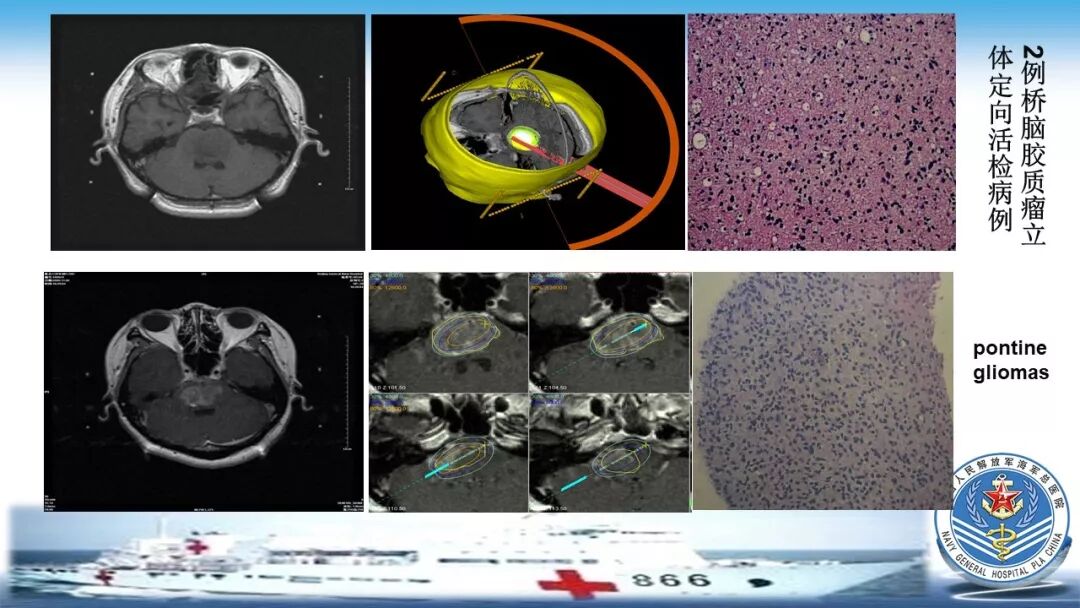

立体定向活检在脑干中线病变精准诊断中的作用

今天为大家带来的是中国人民解放军总医院第六医学中心(原中国人民解放军海军总医院)王亚明、于新、张剑宁带来的精彩课题分享:立体定向活检在脑干中线病变精准诊断中的作用,欢迎观看、阅读!